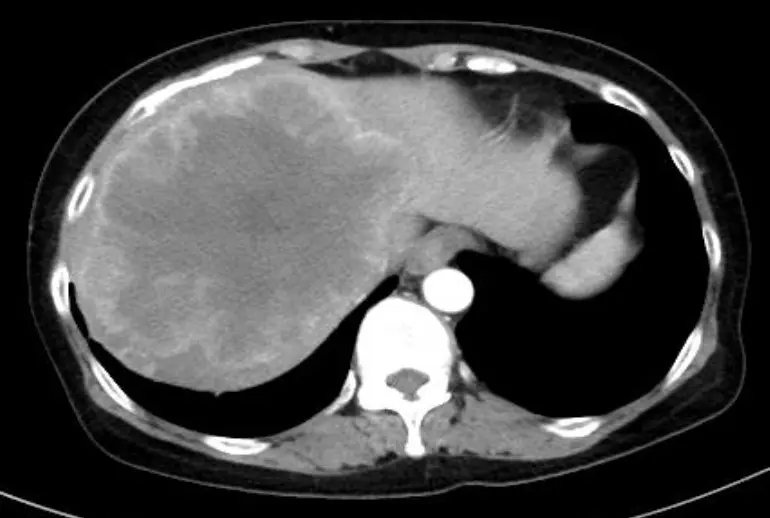

全て 悪性リンパ腫 肉腫 膵臓がん 肛門がん 大腸がん 膀胱がん 胆道がん(胆管がん・胆嚢がん) 脳腫瘍 胃がん 食道がん 胸腺がん 肺がん 頭頸部がん 乳がん 卵巣がん 子宮体がん 前立腺がん 治療実績 症例8 大腸がんステージ4、肝臓を覆い尽くす巨大な転移の消失、主治医、放射線科医も驚く 治療実績 症例1 膀胱癌ステージ4の患者さま。抗がん剤の効果がなく、プレシジョン免疫療法を開始したところすべての転移が消失、腫瘍マーカーも正常化しました。 治療実績 症例5 子宮平滑筋肉腫(再発)、8年間再々発なし 治療実績 症例16 膵臓がんステージ4、当グループが目指す(理想とする)膵臓がん治療プランと経過 治療実績 症例1 肛門管がんステージⅢ、手術・抗がん剤治療は行わず、免疫療法+放射線治療のみで長期安定 治療実績 症例15 30代の患者さま、膵臓がんステージⅢからの克服 治療実績 症例2 前立腺がんステージ4、ホルモン治療+プレシジョン免疫療法で6年間良好にコントロール中 治療実績 症例6 乳がんステージ4、余命半年宣告からの5年お元気